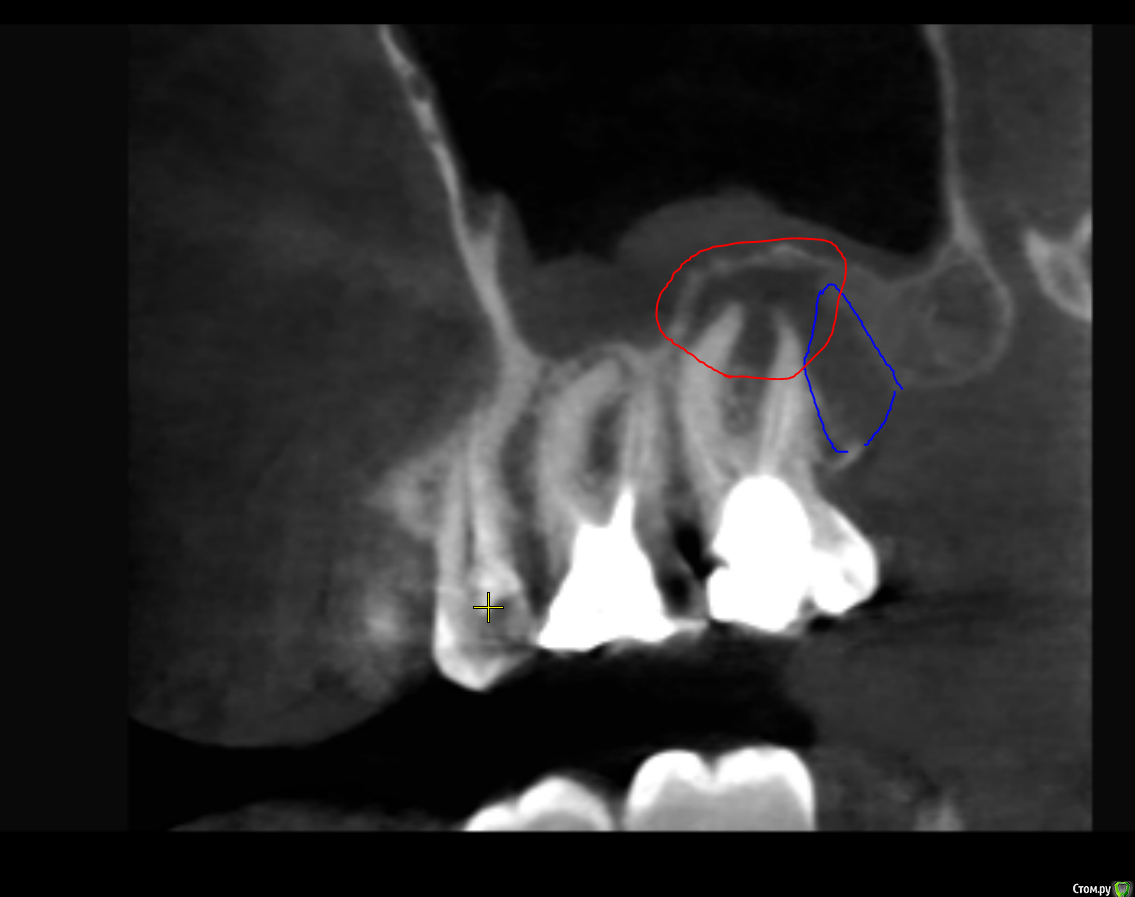

Mightywill Опубликовано 4 ноября, 2020 Поделиться Опубликовано 4 ноября, 2020 (изменено) левый верхний моляр болел только 1 раз, нашли случайно на КТ периодонтит со свищем наружуно кроме того 1 раза никогда не болел больше,через год по полечили каналы,и опять не болел, нет отеков, ничего нет через пол года после лечения каналов зарос свищ (синее на картинке в атаче) но очаг (красное) осталось это первое КТ до лечения вопрос такой:видел в инете фильм Корневая Причина про инфекции в каналах и что такая хрень может давать неожиданные побочки в любом месте тела, а то что там описывалось было прям точь в точь про меня (усталость, тревожность и прочее при нормальных анализах) а у меня еще вдобавок рядом с зубом в ухе шумит, оно часто почемуто более влажное чем правое, и нос начало с какихто пор закладывать еще поэтому я уже год думаю может удалить его нафиг вообще? а не решаюсь потому что сам по себе он ваще никаких проблем не доставляет, не шатается, не болит, дави, стучи - ничего, никаких ощущений поэтому интересно узнать были ли у вас такие случаи когда после кардинального лечения воспаления (через удаление) пацинты говорили что у них неожиданно пропали другие проблемы? Изменено 4 ноября, 2020 пользователем Mightywill 1 Ссылка на комментарий